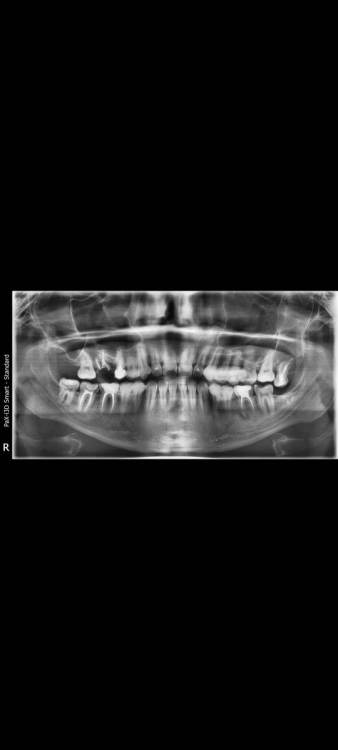

sgusha Опубликовано 16 августа, 2021 Поделиться Опубликовано 16 августа, 2021 Уважаемые специалисты, подскажите, безнадежен ли нижний 36? Врач пугает страшно, грозит удалением. Зуб вообще не беспокоит, киста нашлась на снимке и никак себя не проявляет. Хочу сохранить зуб и ограничится вкладкой, возможно ли это? И подскажите, с верхней шестёркой вообще все пропало? Спасибо огромное за помощь! Ссылка на комментарий

Sier10 Опубликовано 17 августа, 2021 Поделиться Опубликовано 17 августа, 2021 15 часов назад, sgusha сказал: Уважаемые специалисты, подскажите, безнадежен ли нижний 36? Врач пугает страшно, грозит удалением. Зуб вообще не беспокоит, киста нашлась на снимке и никак себя не проявляет. Хочу сохранить зуб и ограничится вкладкой, возможно ли это? И подскажите, с верхней шестёркой вообще все пропало? Спасибо огромное за помощь! Здравствуйте. Рекомендую сделать 3Д снимок обеих челюстей и узнать мнения других специалистов. Судьбу 36 зуба по данному снимку определить невозможно. Если, говоря о верхней шестерке, вы имеете в виду правую сторону, то по данному снимку у зуба одна судьба - на выход. Ссылка на комментарий

St. Опубликовано 19 августа, 2021 Поделиться Опубликовано 19 августа, 2021 Добрый день. Верхний правый 6 без шансов - удалять. Нижний левый 6 - ищите эндодонтиста который возьмется за перелечивание каналов. Шансы на успех есть Ссылка на комментарий